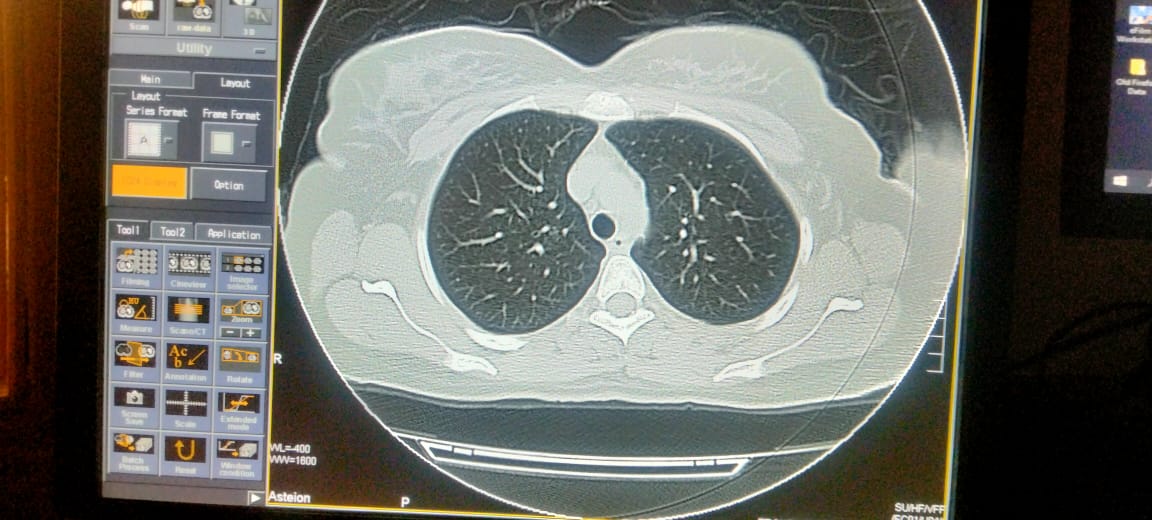

Plz describe it. Film of hrct of corona patient